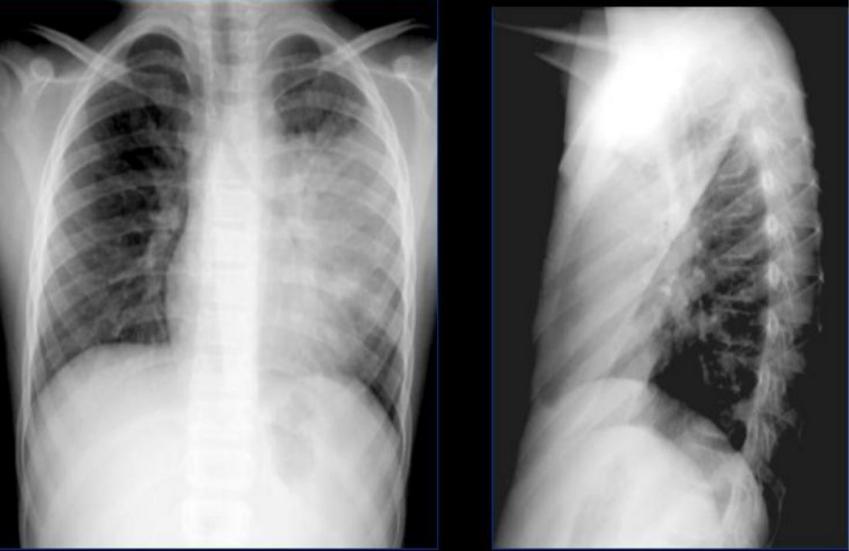

Острая внебольничная пневмония по МКБ-10: признаки и примеры